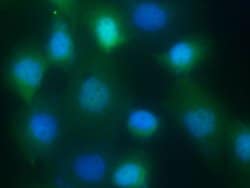

| Flow Cytometry, Immunocytochemistry | |